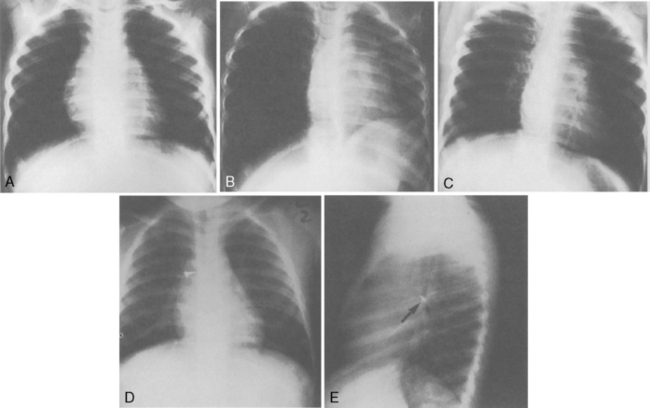

The chest radiograph of a child after drowning may reveal infiltrates and diffuse pulmonary edema (Fig. 9-19). Fractured ribs or air leaks also may be seen as the result of resuscitative efforts.

image